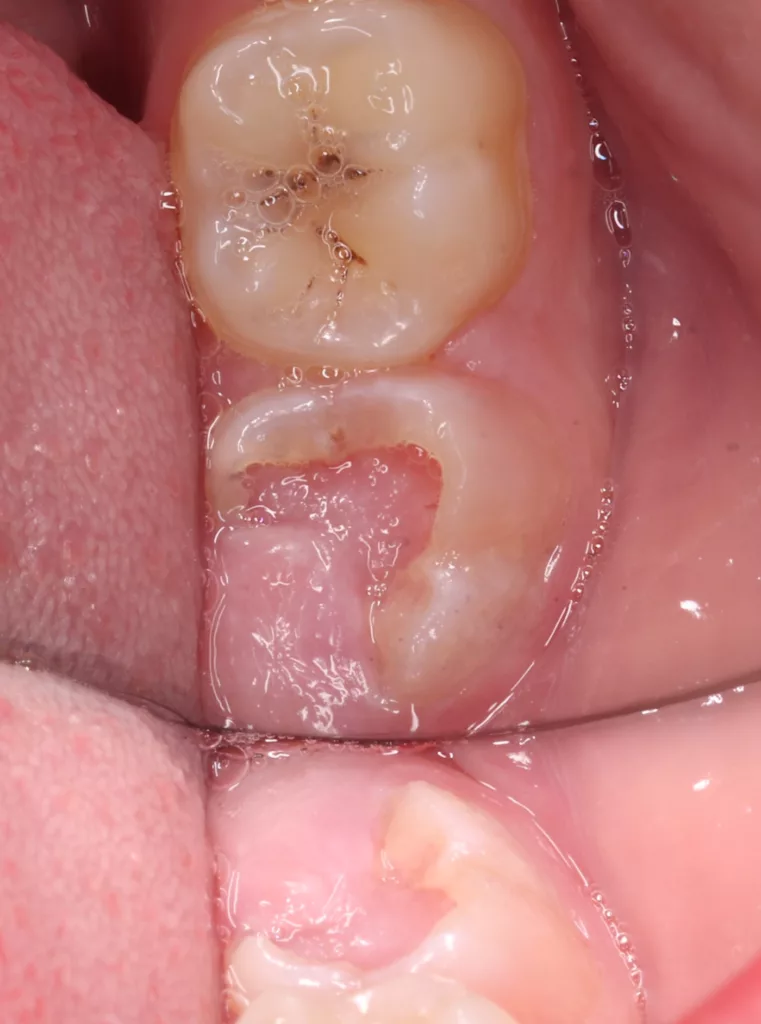

Bei routinemäßigen Röntgenkontrollen ergeben sich manchmal Zufallsbefunde unklarer Genese. So stellt sich beispielsweise bei der Betrachtung der Abbildung 1 die Frage, wie sich ein Zahnhartsubstanzdefekt so schnell entwickeln konnte. Ein weiteres Röntgenbild (Abb. 2), das vor dem Zahndurchbruch aufgenommen wurde, zeigt jedoch, dass es sich in diesem Fall nicht um Karies, sondern um die sogenannte präeruptive intrakoronale Resorption (PEIR) handelt. Für diesen Befund finden sich in der Fachliteratur auch noch andere Bezeichnungen wie „idiopathic external resorption of unerupted permanent teeth“ [1], „intra-follicular caries“ [2], „radiolucent lesions resembling caries“ [3], „occult caries“ [ 4] oder „pre-eruptive caries“ [5].

V. Slabkovskyi, O. Liutikovwährend des Durchbruchs des Zahnes 36.

Das fünfjährige Mädchen stellte sich 2017 zur jährlichen Routinekontrolle vor. Im Rahmen der Untersuchung wurden Röntgenaufnahmen der Milchmolaren gemacht (Abb. 2). Der klinische und radiologische Befund der vor uns früher gelegten Kompositfüllungen war gut, es wurde allerdings eine PEIR an den noch nicht durchgebrochenen ersten bleibenden Molaren festgestellt (Abb. 2). Den Eltern wurde empfohlen, sich unverzüglich bei Beginn des Durchbruchs der ersten Molaren erneut zur Behandlung vorzustellen. Ein Jahr später erschien die junge Patientin schmerzfrei zur Kontrolle. Der Zahn 36 war noch teilweise mit Gingiva bedeckt. Auf einer neuen Röntgenaufnahme (Abb. 1) wurde die PEIR-Läsion mit unveränderter Größe in pulpanahen Bereichen bestätigt (Grad 3 der Läsion nach Seow). Der Zahnschmelz sah intakt aus, es konnte kein pathologischer periapikaler Befund bei den noch nicht ausgewachsenen Zahnwurzeln festgestellt werden. Daraufhin wurden die verschiedenen Behandlungsmöglichkeiten von Fissurenversiegelung bis Vitalerhaltung der Zahnpulpa mit den Eltern des Kindes besprochen.